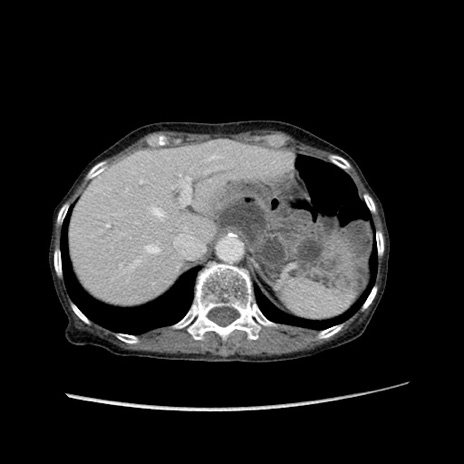

冠状断像

【症例】80歳代女性

【主訴】胸のつかえ感

【現病歴】約9時間前に食後から胸のつかえた感じあり、嘔吐あり、来院。

【既往歴】胃癌(全摘)、胆摘、虫垂炎

【身体所見】心窩部に圧痛あり、反跳痛なし。

【データ】WBC 5700、CRP 0.05